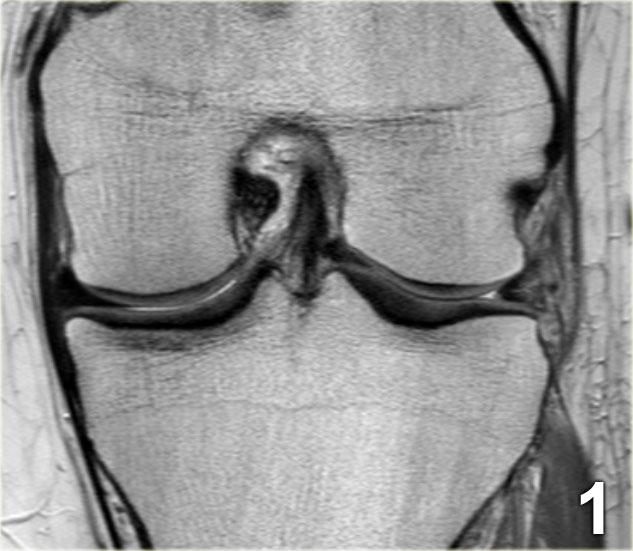

Chúng ta bắt đầu với lát cắt ở giữa của khảo sát.

Lưu ý thân sụn chêm bên có kích thước nhỏ với hình dạng bất thường (mũi tên xanh).

Phần bờ trong bị khuyết được nhìn thấy ngay phía ngoài dây chằng chéo trước (mũi tên đỏ). - Phần sụn chêm bị rách di lệch vào trong, tức là phần quai xách, có thể được theo dõi theo hướng ra sau trong hố gian lồi cầu.

- Tiếp tục.

- Đây là điểm nối giữa phần quai xách và sừng sau.

- Đây là lát cắt phía trước cho thấy một nang sụn chêm.

- Lưu ý tín hiệu cao theo chiều ngang.

- Tại đây chúng ta có thể nhận thấy sự phức tạp của tổn thương rách sụn chêm với thành phần theo chiều dọc và chiều ngang (các mũi tên).

Rách kiểu quai xách là loại rách dọc theo chiều đứng có kèm di lệch.

Mảnh bờ trong bị di lệch có hình dạng giống như quai của một chiếc xô.

Phần ngoại vi còn lại của sụn chêm, phần lớn hơn, có hình dạng giống như thân chiếc xô.

Loại rách này chiếm khoảng 10% trong tổng số các trường hợp rách sụn chêm.

Dấu hiệu PCL đôi

Dấu hiệu dây chằng chéo sau (PCL) đôi là một dải giảm tín hiệu nằm song song và ở phía trước-dưới so với PCL trên ảnh MRI mặt phẳng đứng dọc.

Đây là dấu hiệu có độ đặc hiệu cao trong chẩn đoán rách sụn chêm kiểu quai xô (3).